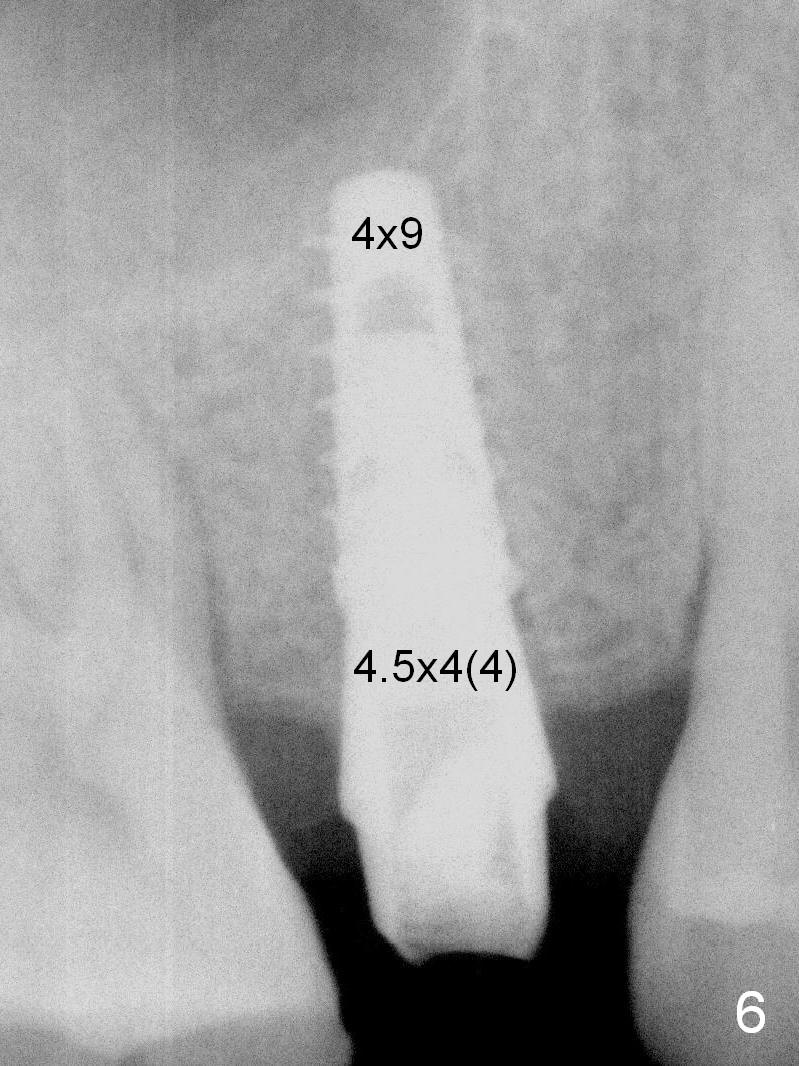

A 47-year-old man returns emergently with subgingival fracture of the lingual (L) cusp of the tooth #4 (Fig.1-3).  After extraction (no bony defect) without drilling, a 4x11 mm dummy implant is placed as a tap drill with satisfactory stability (Fig.4,5).  To get subcrestal placement, a shorter (4x9 mm) implant is inserted with insertion torque of < 35 Ncm.  In retrospect, a larger implant (4.5 mm) would be better in term of primary stability.  After allograft placement into the buccal and lingual gaps, a 4.5x4(4) mm abutment is placed for an immediate provisional.  There is a peri-implant gap 7 months postop (Fig.7<, as compared to the implant at #2 (6 months postop)) .  When the loose abutment is being retightened, the patient feels pain, although the gingiva appears healthy (Fig.8).  A larger implant should have been used; the abutment should have been removed.  The implant dislodges while the abutment is untightened 8 months postop.  The osteotomy is found intact.  A 4.5x11 mm dummy implant is placed 2 mm subgingival with 20 Ncm (Fig.9).  When a 4.5x11 mm definitive implant is placed 3 mm subgingival (Fig.10,11), torque reaches 50 Ncm.  A 5.5x3 mm healing abutment is placed.  Three months postop, the implant is stable (Fig.12,13) and impression is taken.